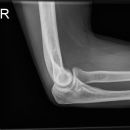

Ellenbogen seitlich (2. Ebene radio-ulnar)

Weitgehend freie Projektion des Radiusköpfchens, das sich als Oval abzeichnet, lediglich vom Processus coronoideus anteilig überlagert. Unterarm darf nicht abhängen.

Qualitätskriterien

Ellenbogengelenk vollständig seitlich orthograd abgebildet. Humeroulnar Gelenkspalt einsehbar. Humeruskondylen müssen sich decken, das Radiusköpfchen soll gut beurteilbar sein.